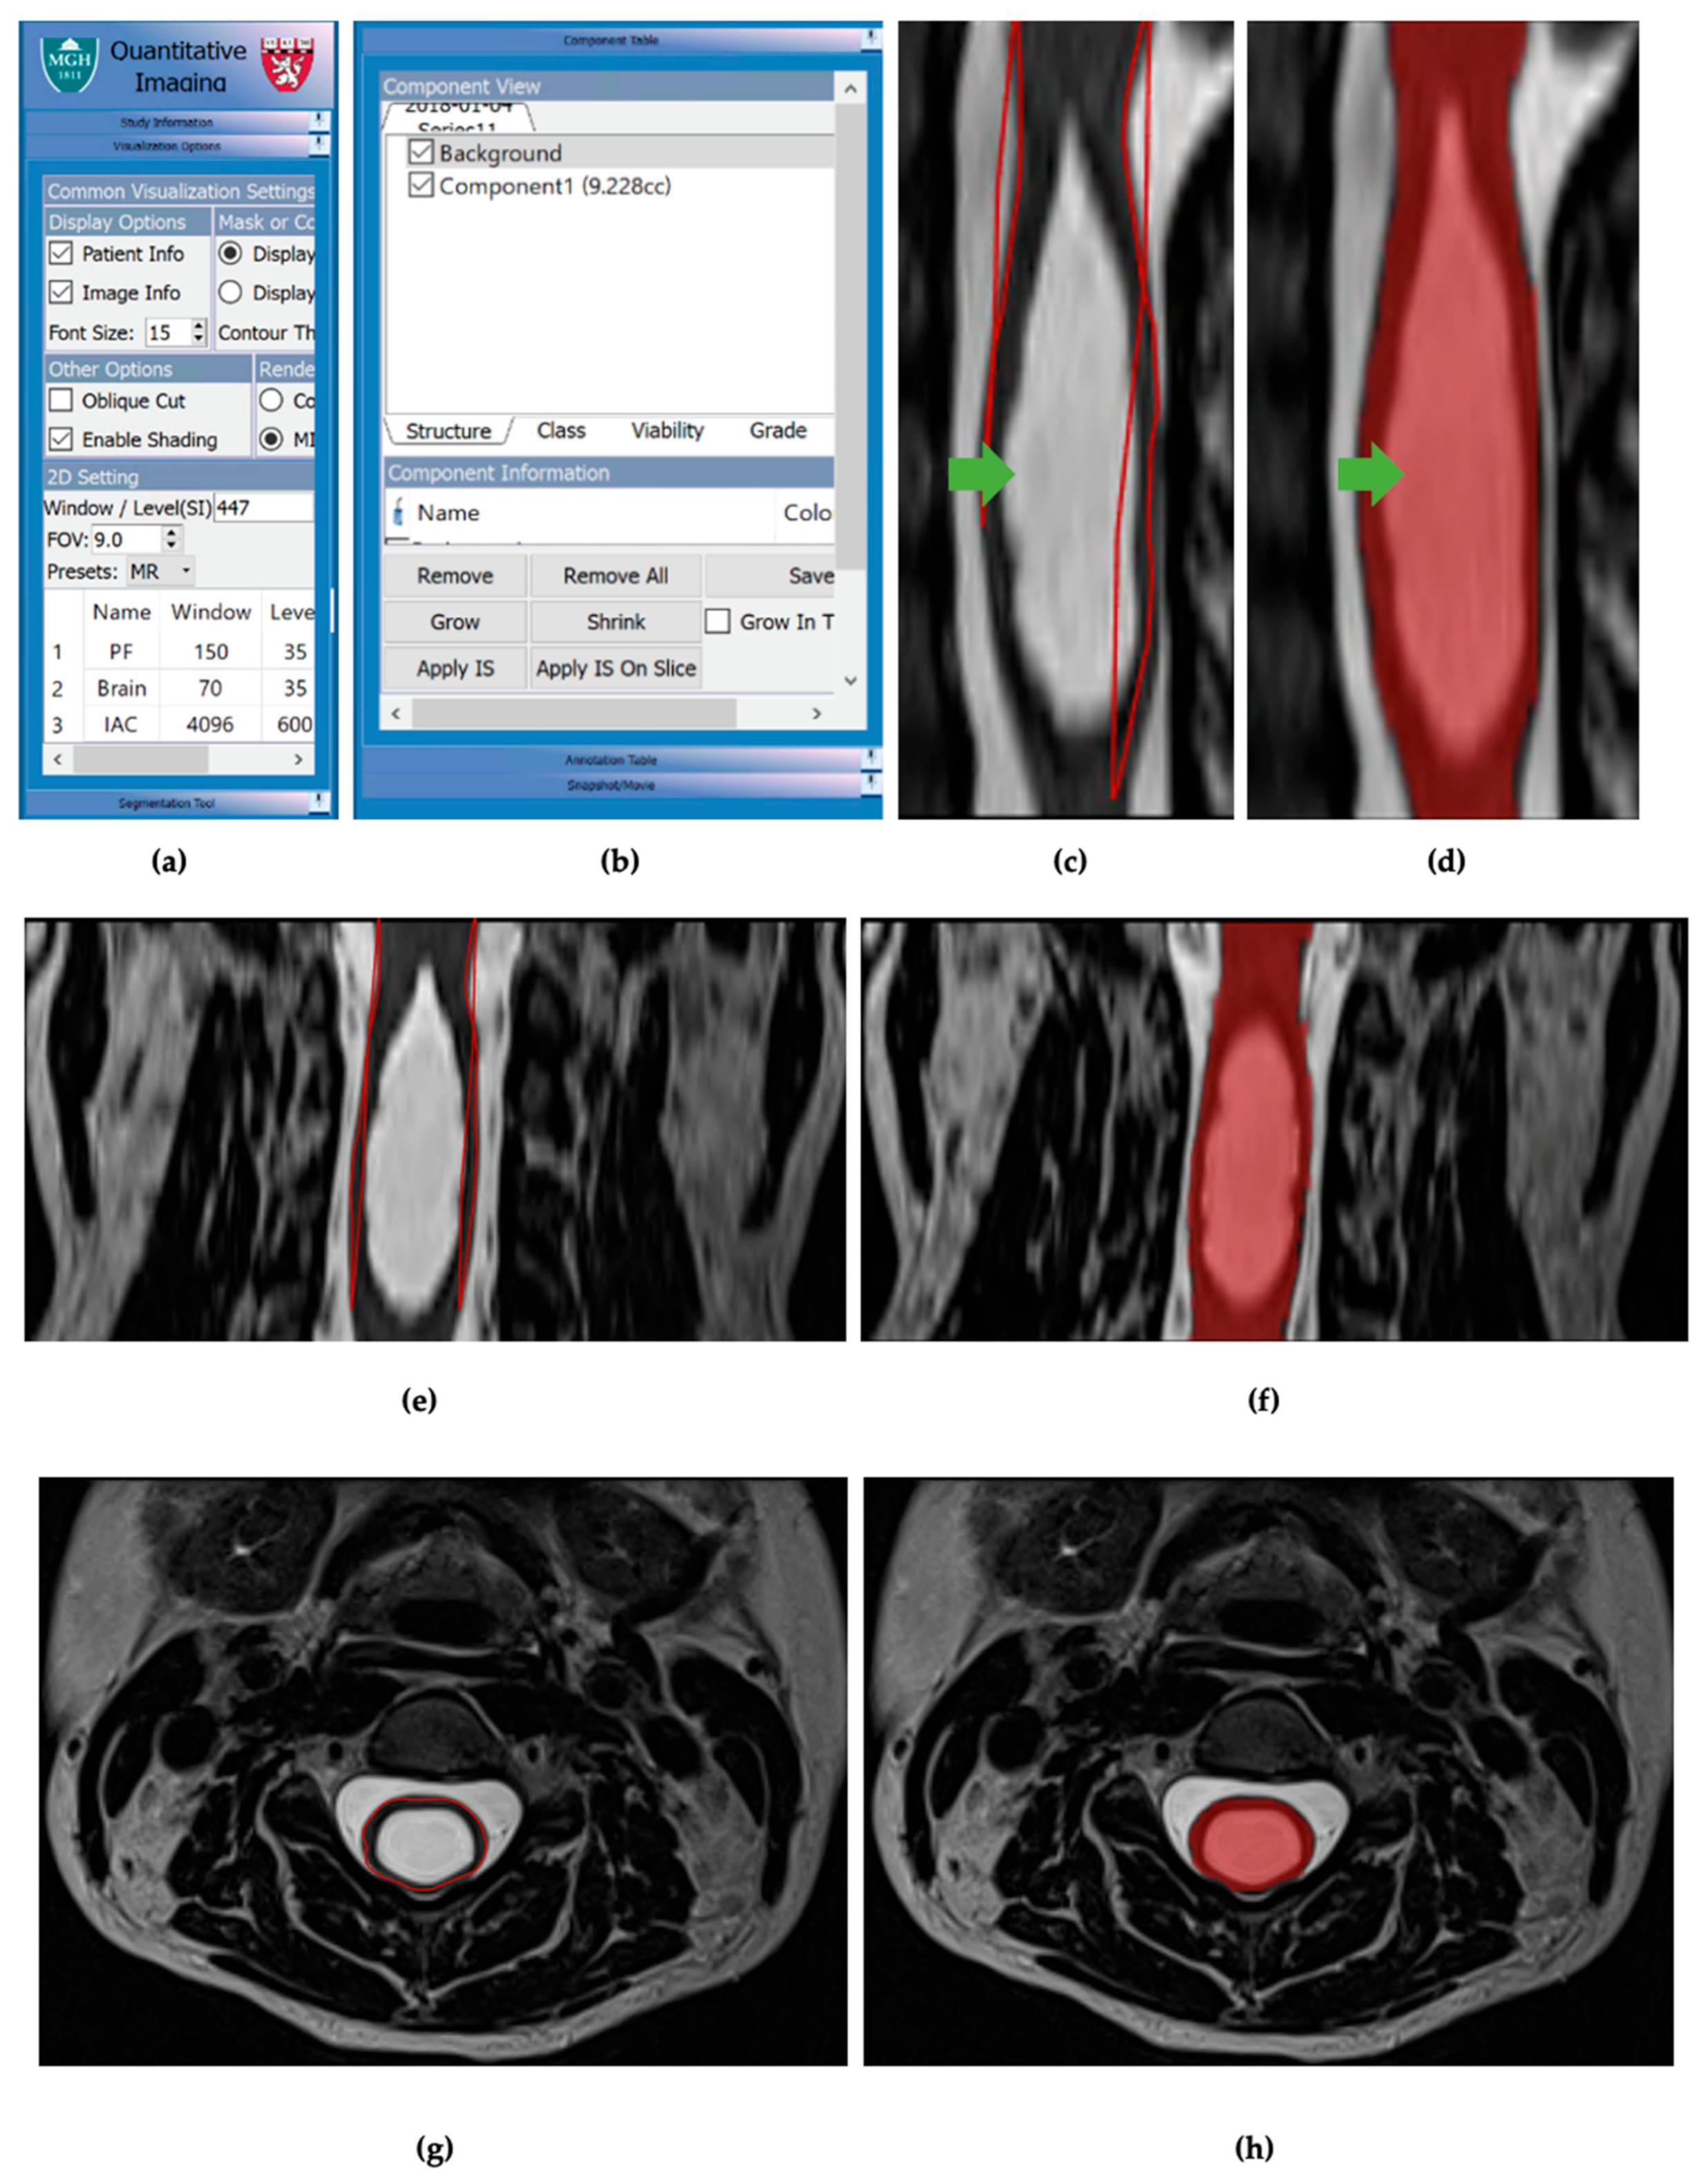

2.4. Three-Dimensional Quantitative Imaging Technology (3DQI) Method of Analysis